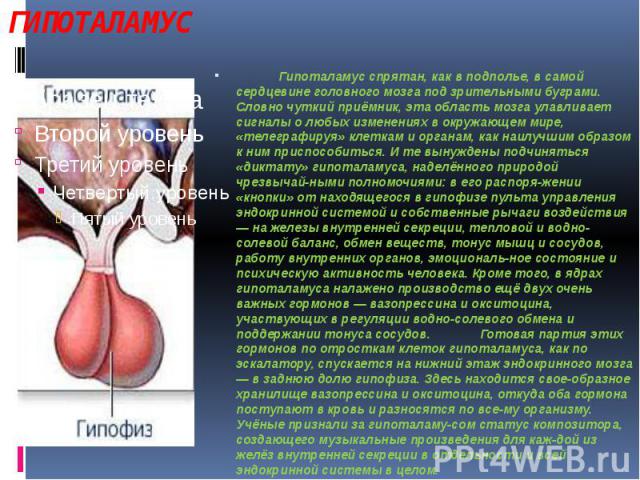

Как работает центр насыщения в гипоталамусе: визуальные иллюстрации